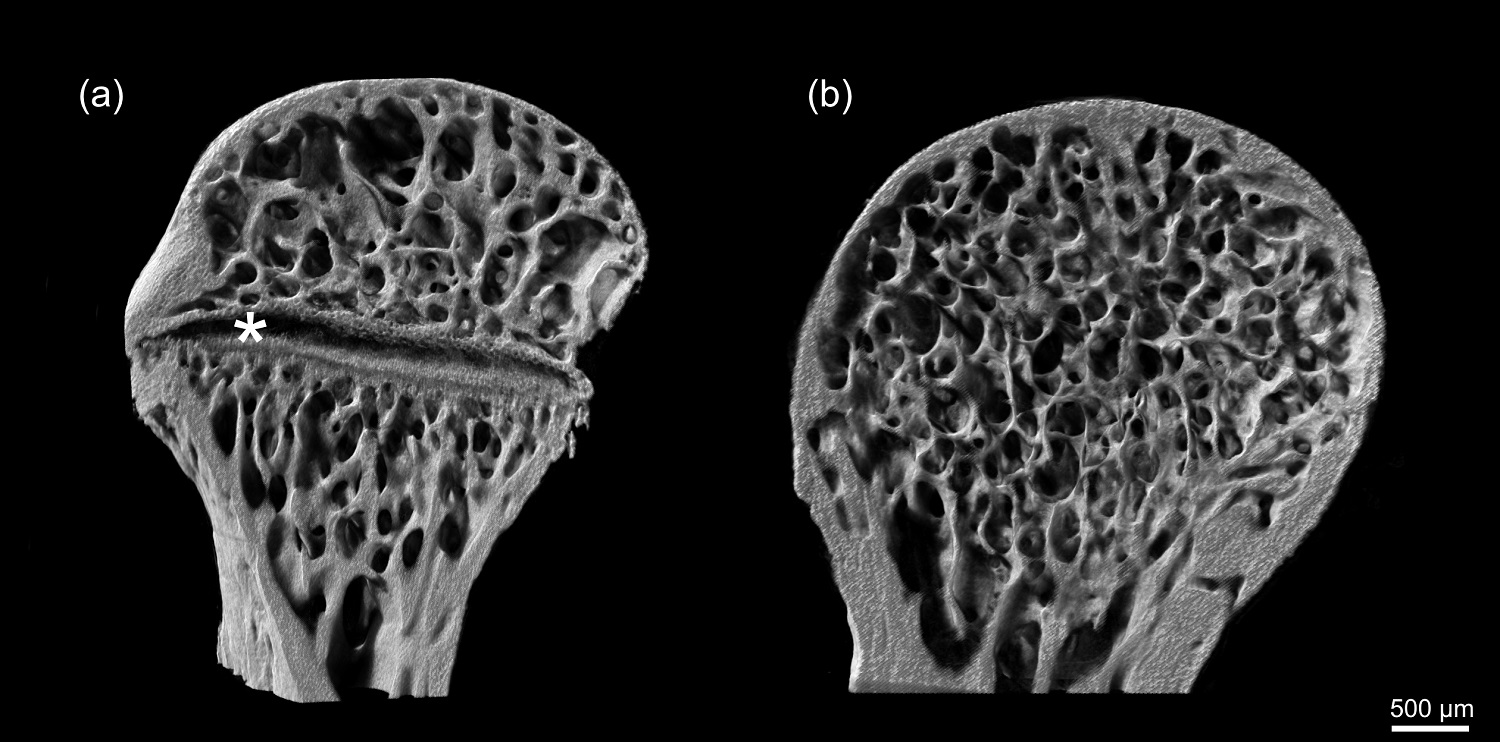

Dá se to tak říci (se shovívavým úsměvem). Zaměřili jsme se na analýzu přítomnosti takzvané růstové ploténky v končetinách šupinatých plazů – Squamata (největší řád plazů s téměř 11000 druhy – pozn. red). Právě tato ploténka je totiž nezbytná pro růst dlouhých kostí, jako je například kost stehenní. Jde o chrupavčitou strukturu ve vnitřní architektuře kosti, která se dá v detailu zobrazit metodou rentgenové mikrotomografie - µCT. Bez růstové ploténky není kost schopná do délky růst. U savců vede její nevratné vymizení k definitivnímu ukončení růstu.

Podélný řez proximální epifýzou stehenní kosti zachycený pomocí rentgenové mikrotomografie s přítomnou (a) a resorbovanou (b) růstovou ploténkou. Hvězdička značí přítomnost růstové ploténky